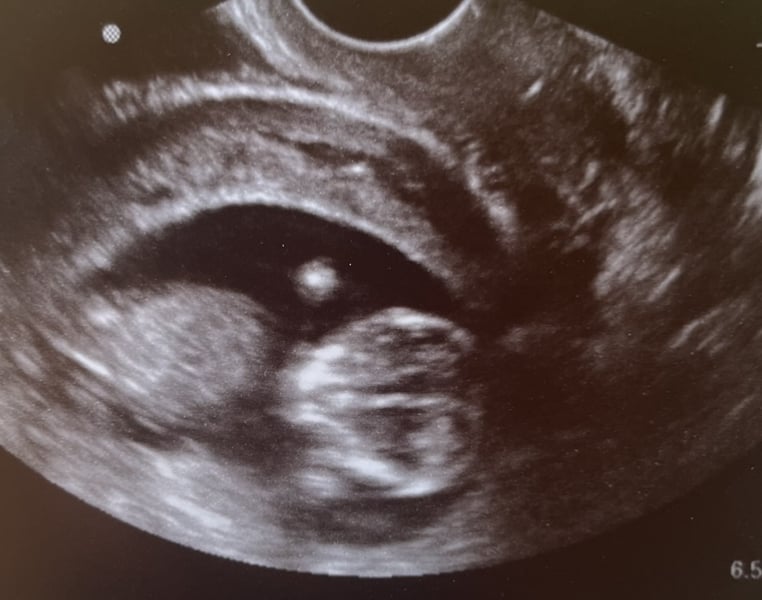

Big yawn, little girl! 20 weeks + 1 day (last Thursday) Estimated about 9 ounces, measuring about a week and a half behind after being right on track earlier in the pregnancy. Placental insufficiency, absent end-diastolic flow, growth restriction... but she was very active during the scan and that is very positive. We'll be doing another scan at 23 weeks and we'll see where we go from there.

Big yawn, little girl!

20 weeks + 1 day (last Thursday)

Estimated about 9 ounces, measuring about a week and a half behind after being right on track earlier in the pregnancy.

Placental insufficiency, absent end-diastolic flow, growth restriction... but she was very active during the scan and that is very positive. We'll be doing another scan at 23 weeks and we'll see where we go from there.